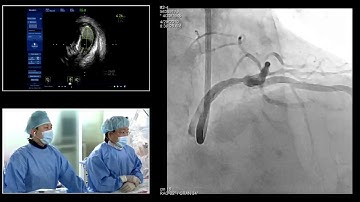

[TCTAP 2019] Master the CTO - Live Case & Lecture Session I